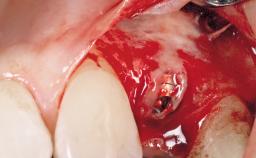

Immediate Flapless Placement of an Implant in a Maxillary Right Lateral Incisor Site

This 43-year-old male patient, a non-smoker, came to our practice because of a fracture of tooth 12 caused by a bicycle accident. Due to the combined para- and infrabony crown and root fracture, tooth extraction, and subsequent implant placement were suggested to the patient as the therapy of choice. The patient had high esthetic expectations with regard to the treatment outcome and asked for an immediate fixed provisional restoration. His individual esthetic risk profile summed up to a medium esthetic risk.

Placement Protocol Immediate implant placement

Socket Morphology Single-root socket

Socket Integrity Sufficient, with intact bone walls